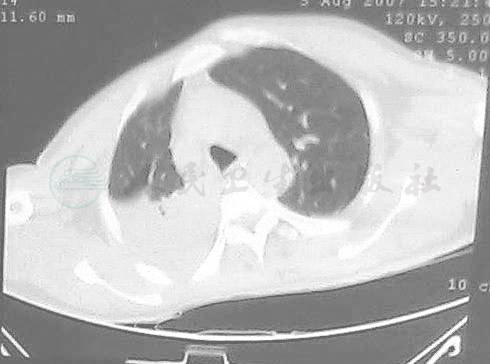

患者,男,59岁,因“外伤后昏迷1个月,反复咯血4天”入院。诊断:①重度颅脑损伤、脑挫裂伤、急性硬膜下血肿、脑内血肿,颅内血肿清除术并去骨瓣减压术后;②多发肋骨骨折并右肺不张;③肺部感染并大咯血;④气管切开术后;⑤冠心病。查体:T 38.7℃,P 112次 /分,R 20次 /分,BP 128/75mmHg。昏迷状态,两侧瞳孔等大等圆,直径3mm,对光反应迟钝,气管切开,右肺呼吸音低,两肺闻及干啰音。心律齐,心率96次/分,未闻及杂音。双上肢肌力0级,右下肢肌力Ⅰ级,左下肢肌力Ⅴ级,右Babinskin征(+)。胸部CT示右上肺实变(图1)。

图1 右上肺实变